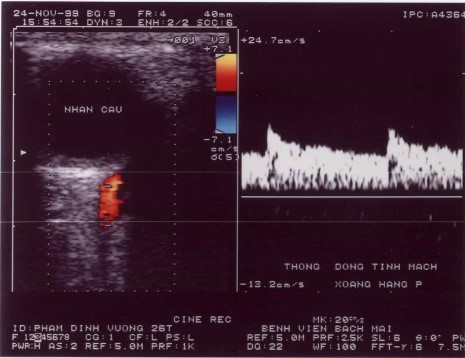

3